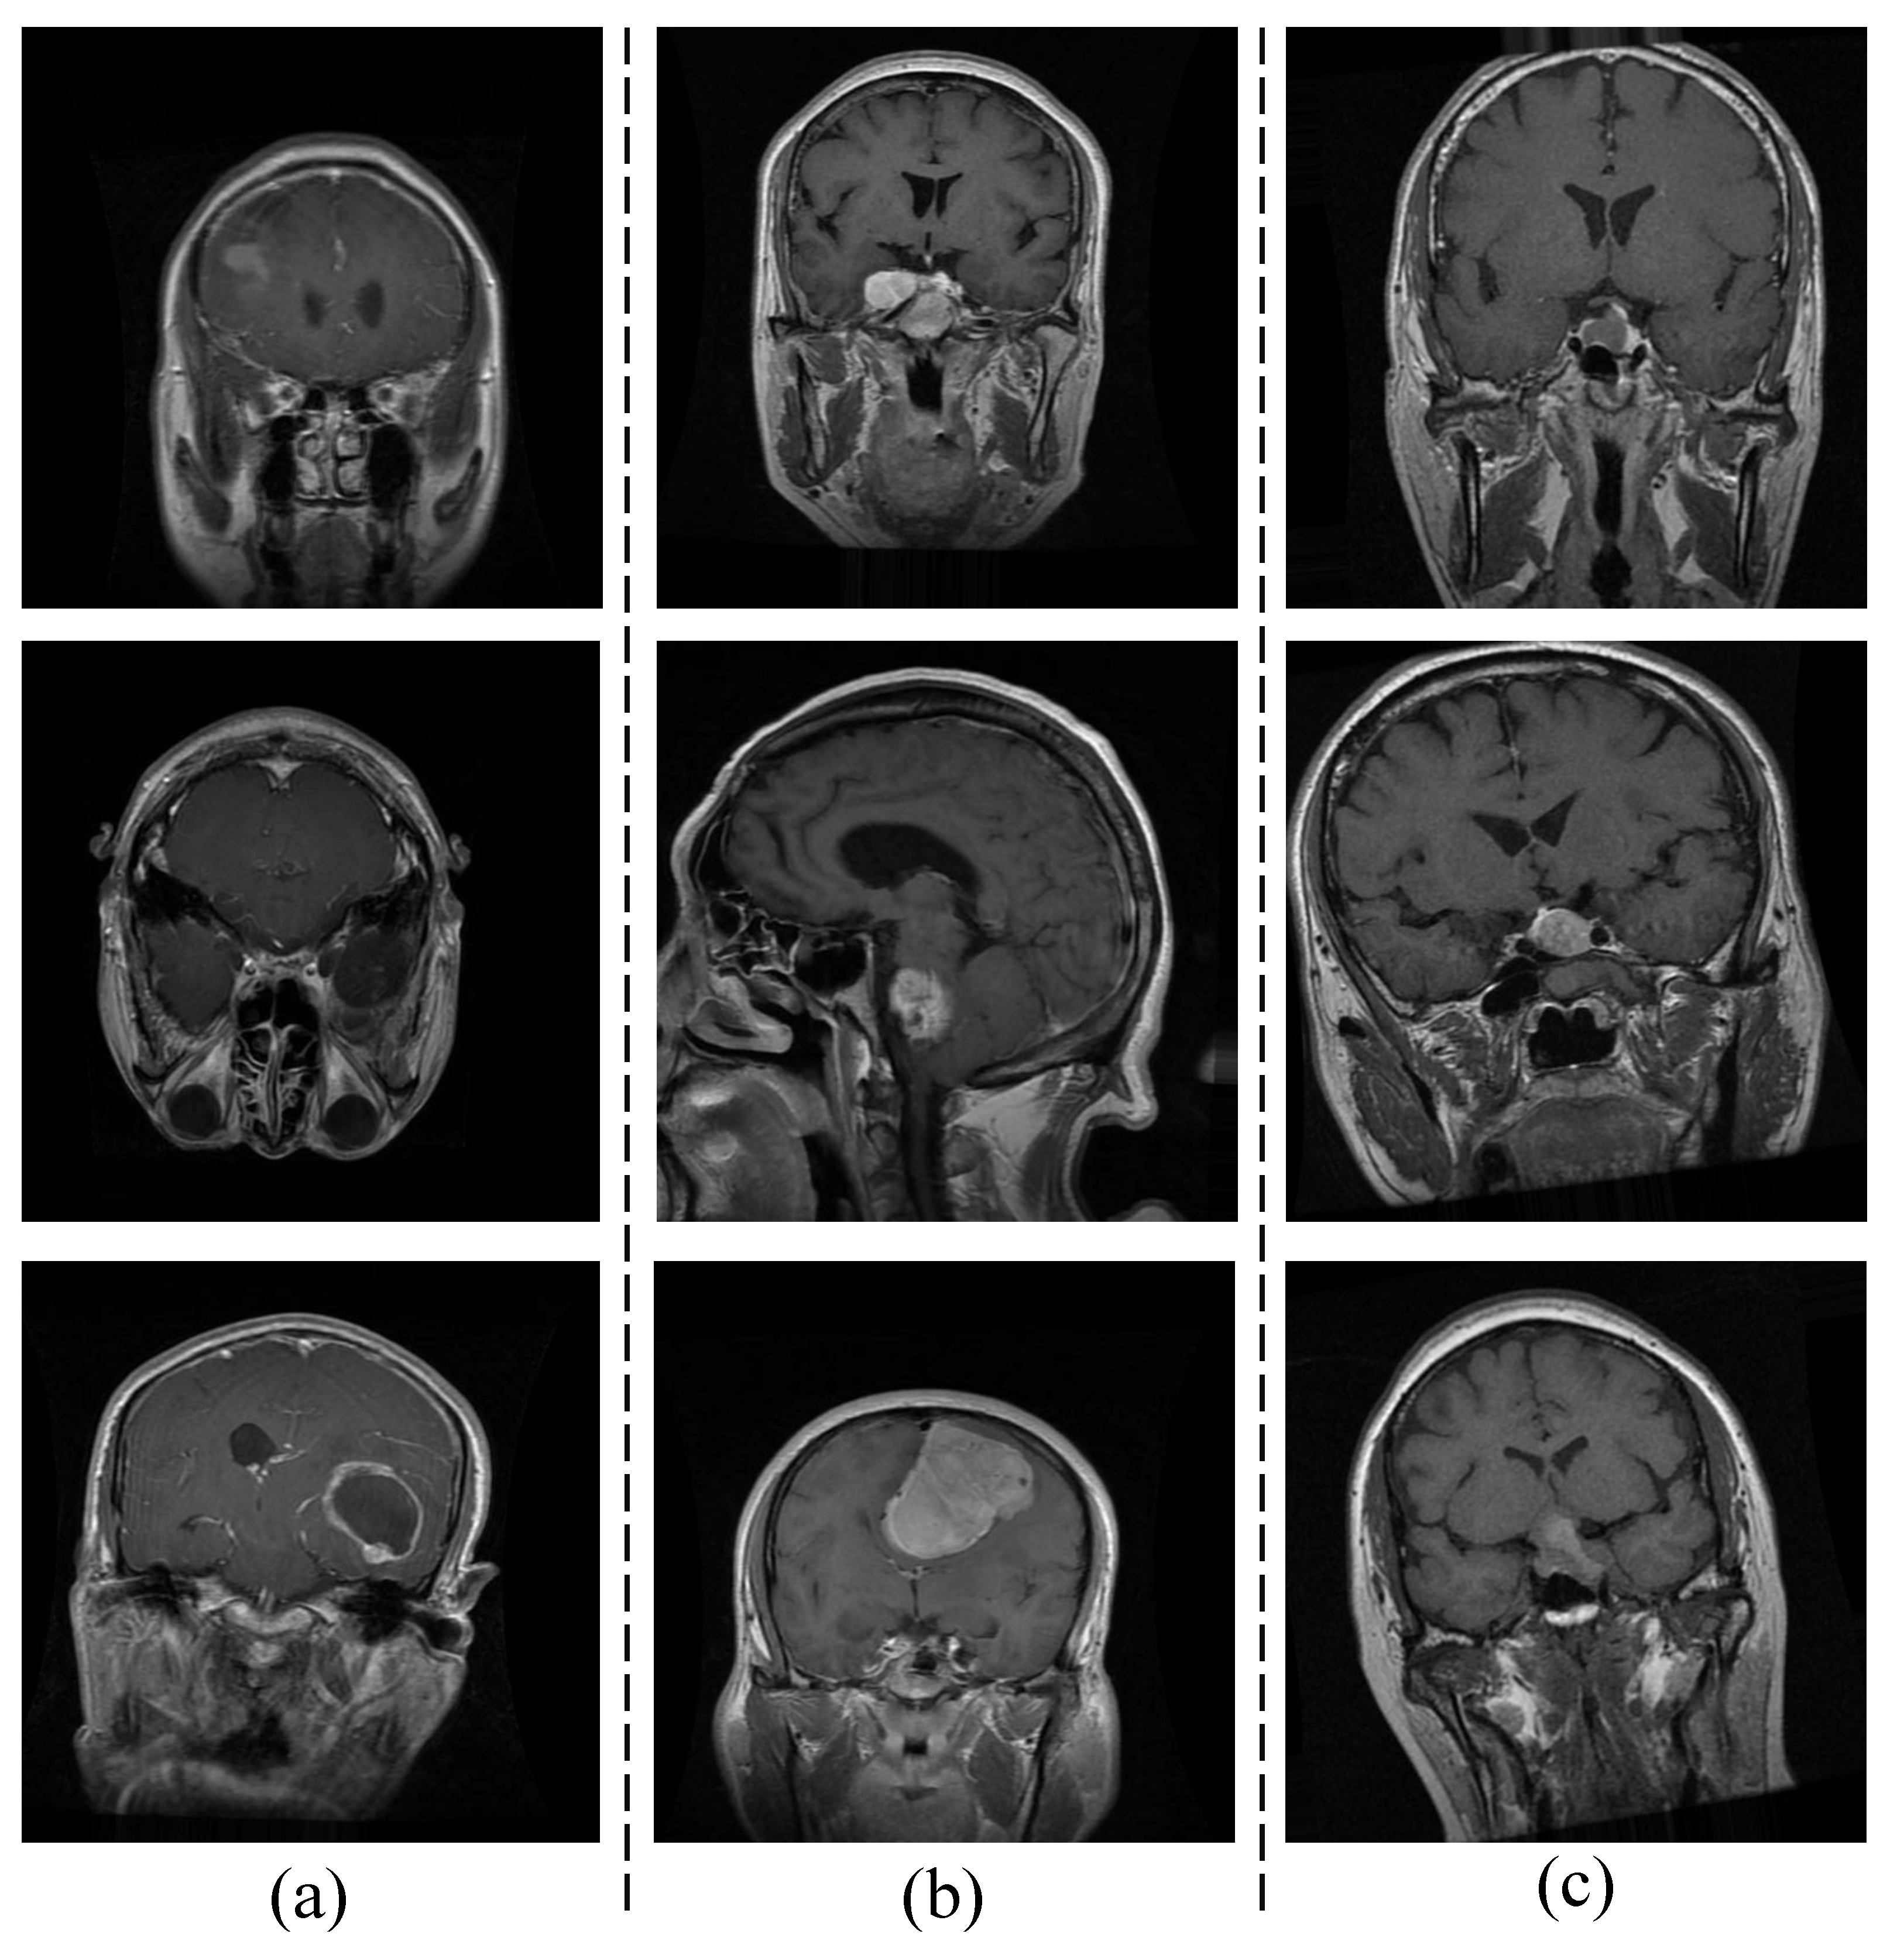

Initially, the dataset consisted of 3064 T1-weighted, contrast-enhanced images derived from 233 patients who presented with three distinct types of brain tumors: meningioma (comprising 708 slices), glioma (comprising 1426 slices), and pituitary tumors (comprising 930 slices) [40]. Obuli [41] meticulously compiled this dataset, ensuring that each category contained 5000 images. Figure 1 displays sample images representing three distinct brain tumor types—(a) glioma, (b) meningioma, and (c) pituitary tumor—which were obtained from the dataset compiled by Obuli [41].

Figure 1.

Sample images: (a) Glioma, (b) Meningioma, and (c) Pituitary Tumor.